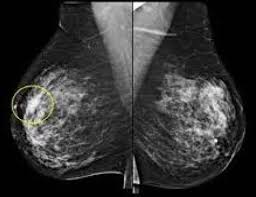

Узловая мастопатия

Статья для справочника портала Медихост

medihost.ru/glossary/diseases/uzlovaya_mastopatiya...